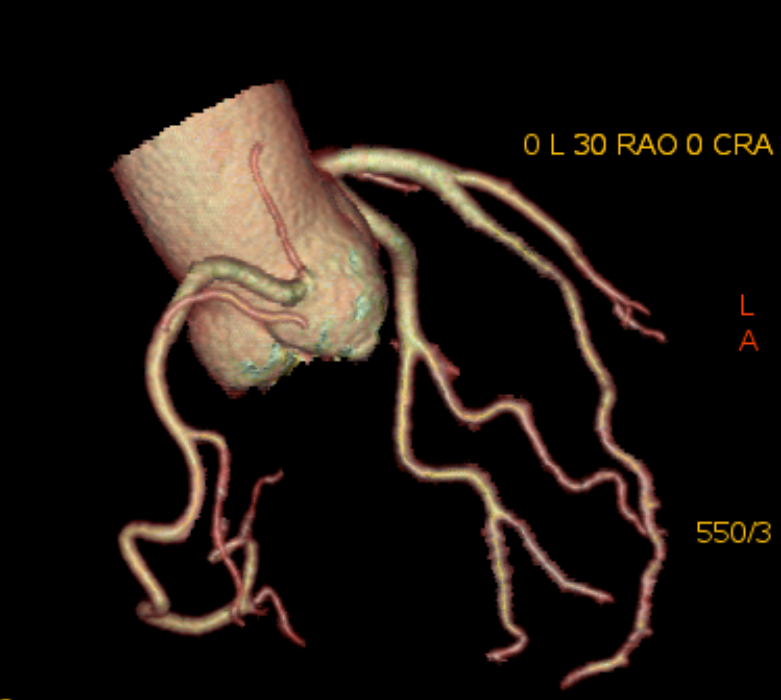

6、心臟CTA是經(jīng)靜脈注射造影劑后進(jìn)行CT快速掃描和圖像重建技術(shù)獲得冠狀動(dòng)脈圖像,以精準(zhǔn)了解冠狀動(dòng)脈是否存在解剖變異、畸形、心肌橋、狹窄,評(píng)估冠狀動(dòng)脈支架或搭橋術(shù)后血管情況等。心臟磁共振檢查具有無(wú)輻射、多參數(shù)、多平面、多序列成像等特點(diǎn),具有良好軟組織分辨力,一次檢查可獲得心臟解剖形態(tài)、心臟功能、血流、心肌灌注或活性、心臟代謝、大血管和冠狀動(dòng)脈的信息,在診斷心肌病方面具有重要意義。

心臟冠脈成像 VR